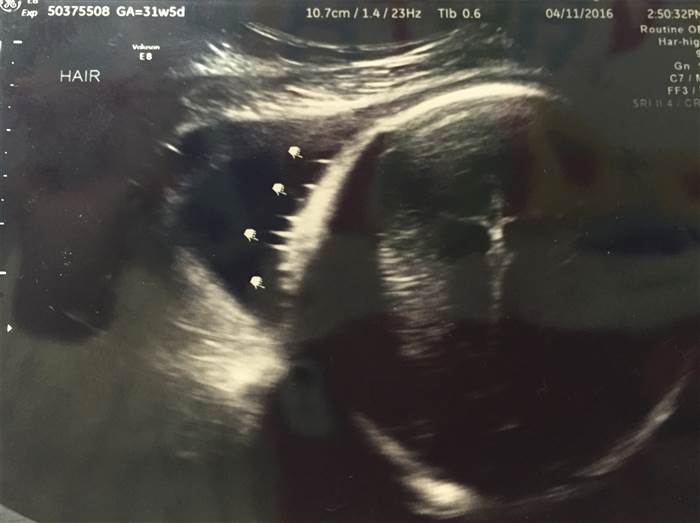

一位即將當媽媽的年輕少婦,罹患上一種發炎性腸道疾病克隆氏症,得服用藥物治療,在一次不尋常出血後,愛莉去照了超音波檢查,不料她發現照片中有

十字架上的

耶穌,頓時驚呆了,但她認為是上帝在庇佑她的孩子。

21歲的愛莉和她的未婚夫即將在六月迎接他們第一個寶寶,但因為愛莉患有克隆氏症,在一次不尋常出血後,愛莉擔心會影響胎兒去照了超音波檢查,後來經過好友提醒,才發現超音波的照片裡出現十字架和耶穌圖樣,愛莉愣住了!盯著照片看了半小時,她未婚夫覺得「恐怖」,但愛莉卻認為這是「神聖的介入」。